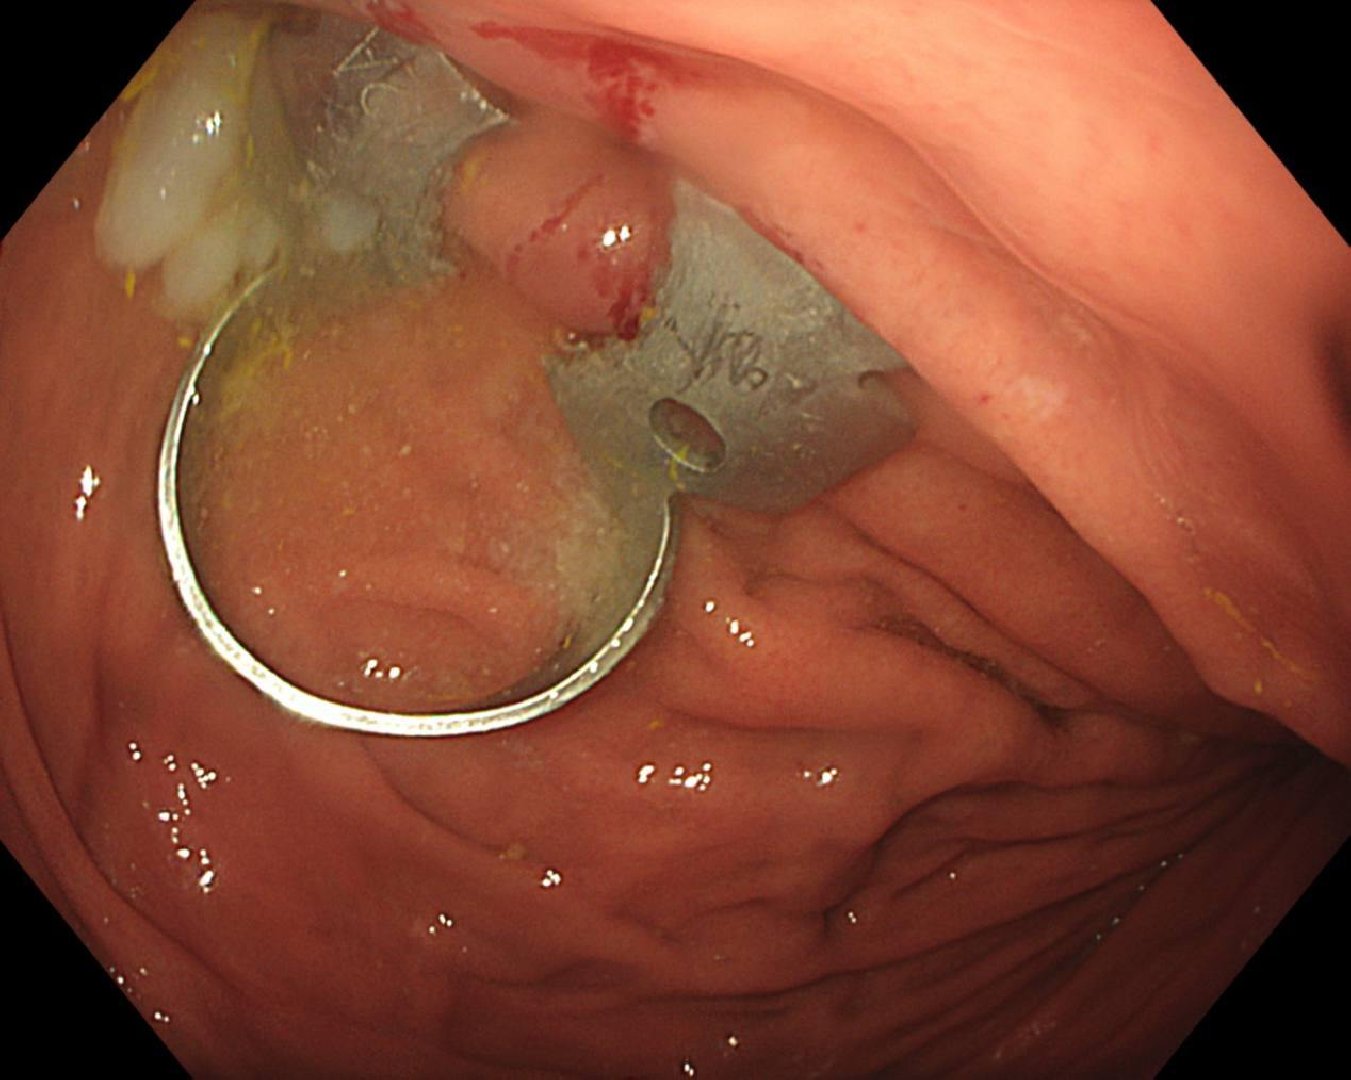

«Для извлечения скобки мы выполнили гастроскопию, в ходе которой захватили инородное тело эндоскопической петлёй. Предмет был острым, и это создавало высокие риски травмировать слизистую. Поэтому мы поэтапно провели скобу через пищевод, его устье и гортаноглотку. Процедура длилась около 10 минут и прошла успешно», – рассказала врач-эндоскопист Анастасия Лазарева.